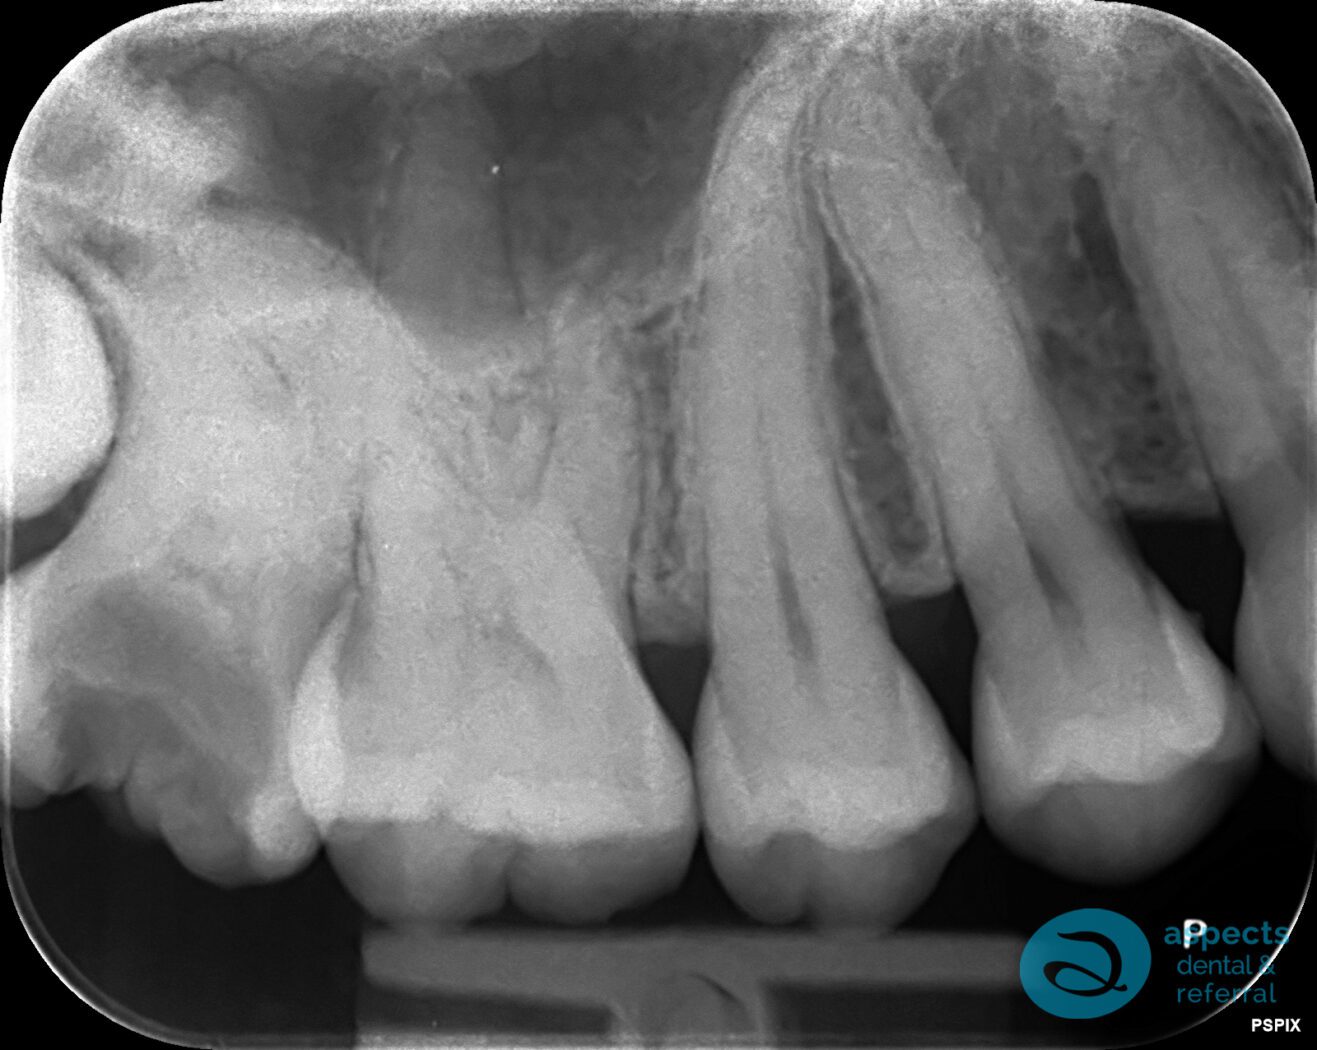

Our Dental Patient presented with a grossly carious tooth exhibiting severely curved roots and in close proximity to the adjacent third molar. Due to the complexity of the root anatomy and position, a surgical tooth extraction was indicated.

Before Surgical Tooth Extraction Xray